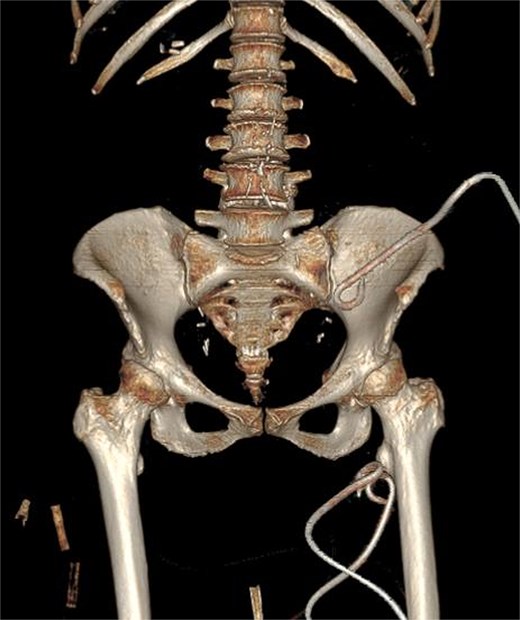

Due to the complex anatomy, a single access was deemed insufficient. Under real-time ultrasound and fluoroscopic guidance, a retroperitoneal approach was first used: an 18-G needle and guidewire were advanced in the left midaxillary line parallel to the iliac crest, followed by tract dilation and placement of a 12-G pigtail catheter into the psoas component. Subsequently, two additional 12G catheters were placed percutaneously via a femoral approach into the thigh extension (Fig. 2). In total, ~200 ml of purulent material was drained. The localization of the drains was confirmed by subsequent CT (Fig. 3).

3D CT reconstruction depicting the final positions of the drainage catheters.